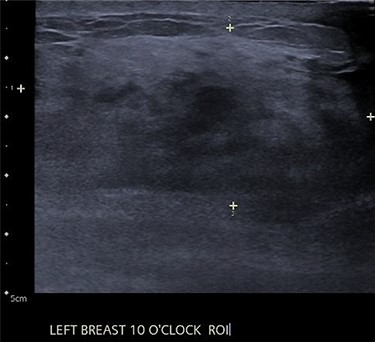

An ultrasound of the left breast demonstrated a 60-mm irregularity with no underlying collection at the 10 O’clock position, 2 cm from the nipple (Fig. 1). AB was treated with 5 days of oral flucloxacillin for presumed mastitis, and underwent a bilateral mammogram and ultrasound due to the suspicious irregularity of the left breast lesion. This showed an area of asymmetric density in the medial left breast with hyperemia (Fig. 2). The right breast showed two clusters of pleomorphic microcalcifications in the upper outer quadrant, further characterized as irregular lesions measuring 16 × 11 × 11 mm and 9 × 10 × 7 mm (Fig. 3).